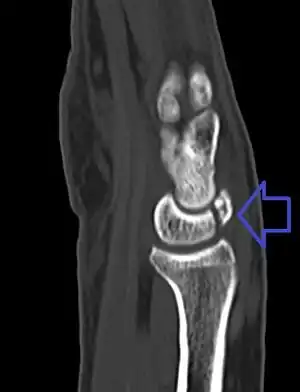

| A lunate fracture as seen on CT scan of the wrist | |